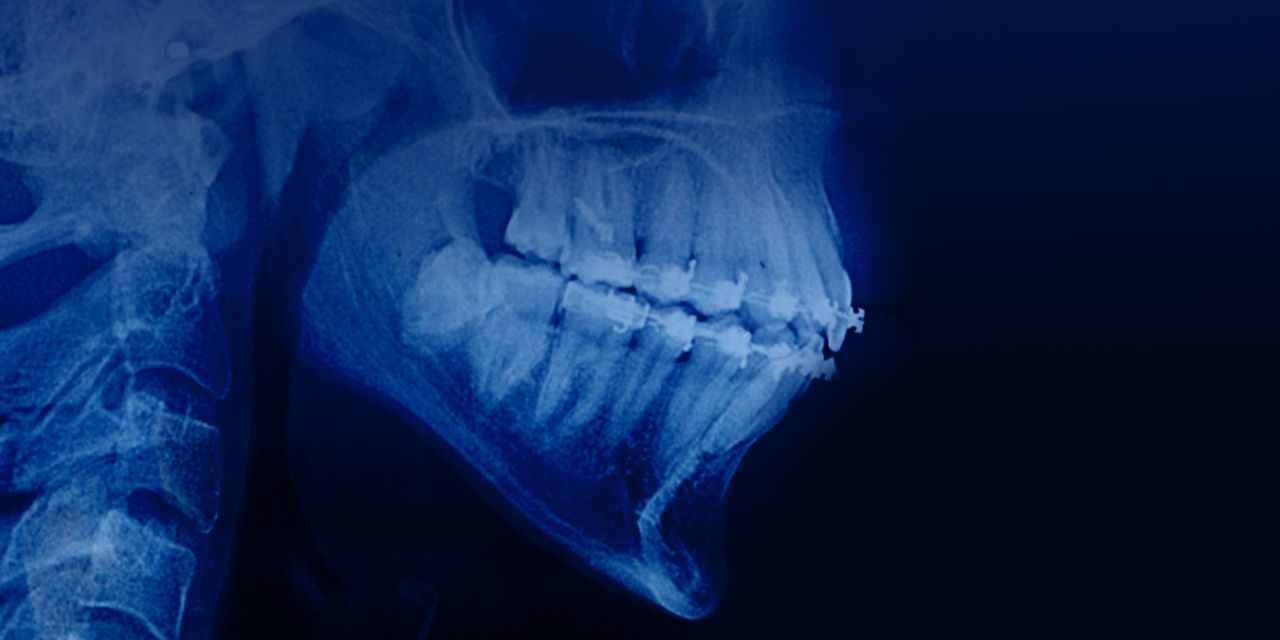

Complex Non Extraction severe crowding and Class III malocclusion with lower molar Distalization